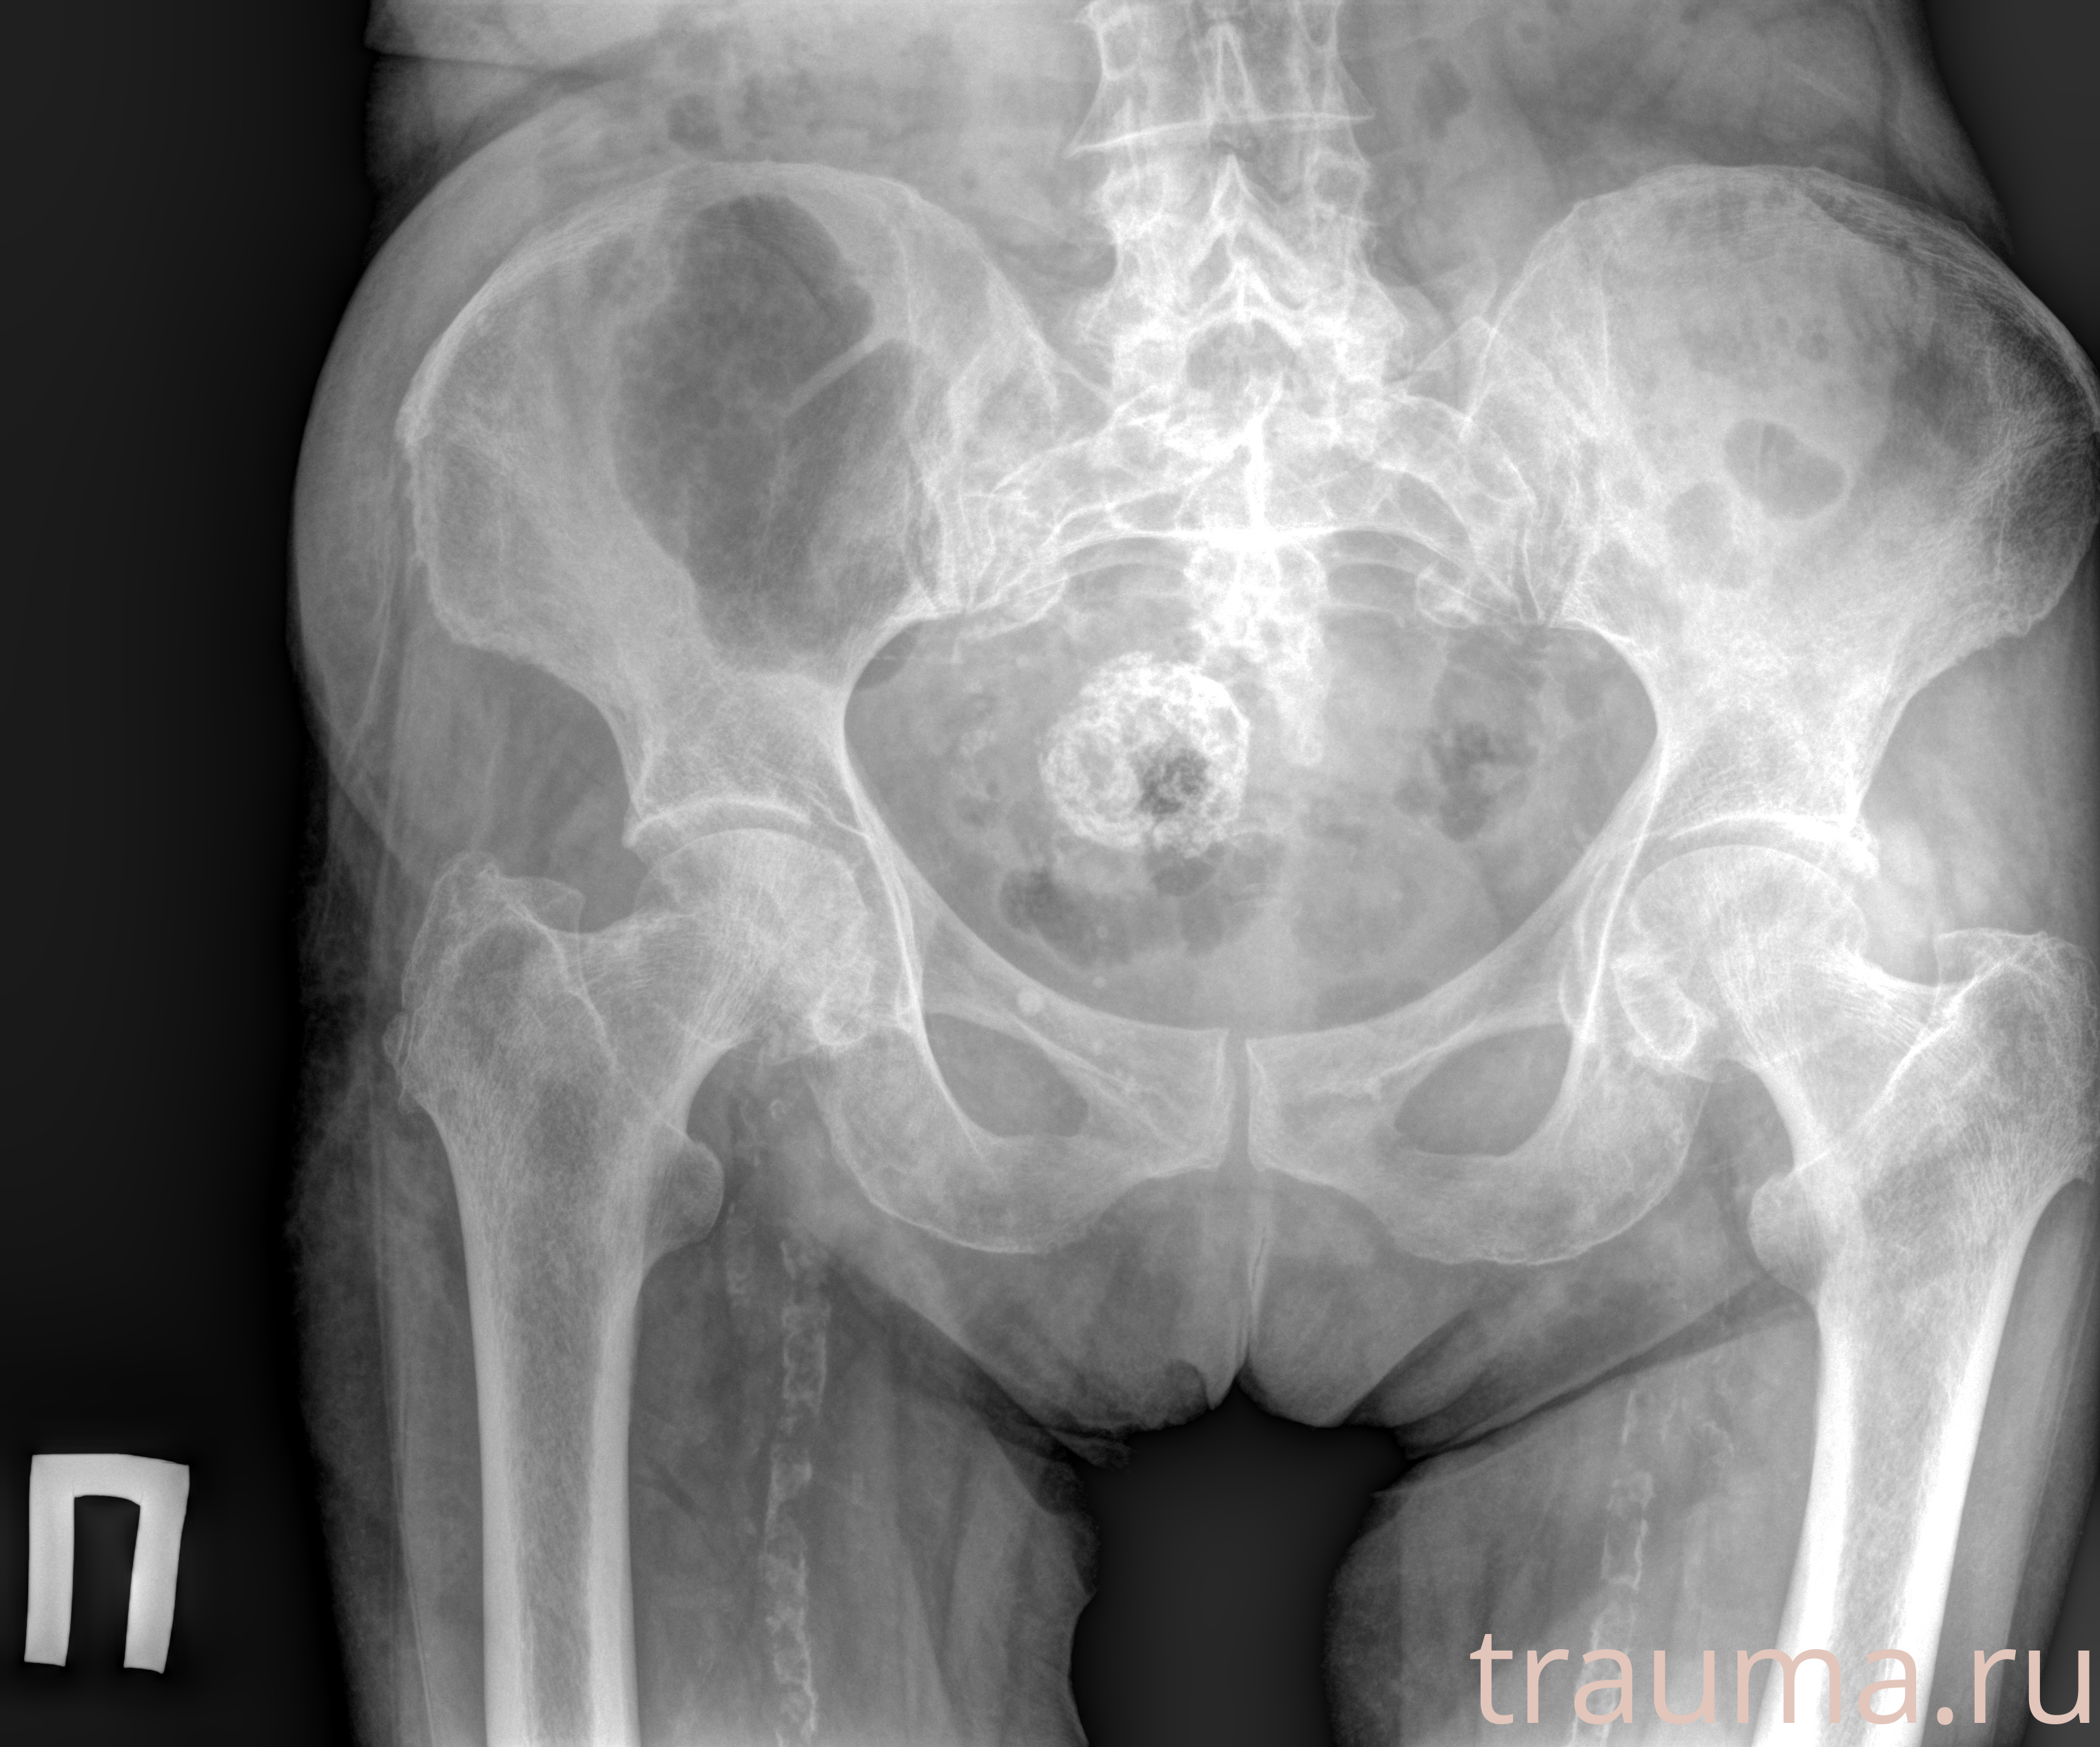

Рентгенограммы

Рентген на дому: по вашему адресу приезжает врач-рентгенолог, травматолог-ортопед с мобильным рентгеновским аппаратом, проводит диагностику травмы или заболевания, делает необходимые рентгенограммы, дает рекомендации по дальнейшему лечению. Получить качественные снимки в домашних условиях возможно благодаря уникальной методике, разработанной МосРентген Центром для института  Склифосовского

Яркость: 1   Контраст: 1   Инвертировать: 0 Увеличение: 1

Перетаскивайте мышь вверх/вниз для контраста, влево/право для яркости. Прокрутка колесом изменяет масштаб. Нажмите Сбросить для возврата к исходному изображению. При увеличении держите мышь в той области, которую хотите рассмотреть.